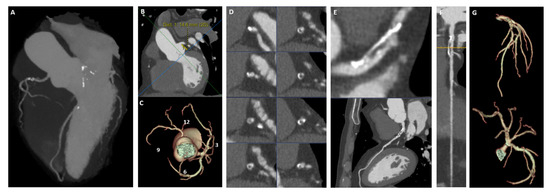

Rationale and Design of the “PRECISION-CT” Study—A Prospective Evaluation of Coronary CTA Integration for Strategy Improvement and Optimization of PCI in Chronic Coronary Syndrome

Background: Coronary computed tomography angiography (CCTA) is a well-established key diagnostic modality for ruling out obstructive coronary artery disease (CAD) in patients with suspected chronic coronary syndromes (CCSs) and low to intermediate pre-test probability. The widespread availability of preprocedural CCTA data in CCS [...] Read more.

Background: Coronary computed tomography angiography (CCTA) is a well-established key diagnostic modality for ruling out obstructive coronary artery disease (CAD) in patients with suspected chronic coronary syndromes (CCSs) and low to intermediate pre-test probability. The widespread availability of preprocedural CCTA data in CCS patients undergoing percutaneous coronary intervention (PCI), however, creates a new opportunity for image-guided procedural planning. Objective: The PRECISION-CT study (Prospective Evaluation of Coronary CTA Integration for Strategy Improvement and Optimization of Non-Emergent PCI) aims to evaluate the impact of CCTA-guided PCI on patient safety and clinical outcomes. Methods: PRECISION-CT is a prospective, two-center, randomized controlled trial, enrolling patients with CCS scheduled for elective PCI due to obstructive CAD by CCTA. Patients are randomized 1:1 to either CCTA-guided PCI or standard angiography-guided PCI. In patients randomized to CCTA-guided PCI, advanced post-processing of CCTA datasets provides specific procedural planning recommendations based on the detailed assessment of coronary artery takeoff, lesion location and plaque characteristics. In addition, real-time integration of the advanced CCTA post-processing is available in the catheterization laboratory during the PCI procedure. Patients randomized to angiography-guided PCI are treated according to routine clinical practice. Results: The primary endpoint is a composite procedural safety and efficacy score including: (i) need for intravascular imaging, (ii) procedural complications, (iii) post-procedural high-sensitivity troponin T elevation, (iv) contrast media, (v) radiation exposure, and (vi) length of hospital stay. Secondary endpoints include major cardiac adverse events such as cardiac death, non-fatal myocardial infarction, target-lesion reintervention and probable or definitive stent thrombosis during 1 year of follow-up. Conclusions: The PRECISION-CT study will provide pragmatic evidence on the ability of CT-guided PCI in patients with CCS to optimize procedural outcomes. These findings may help inform the broader adoption of image-guided precision revascularization strategies in interventional cardiology. Full article

Figure 1